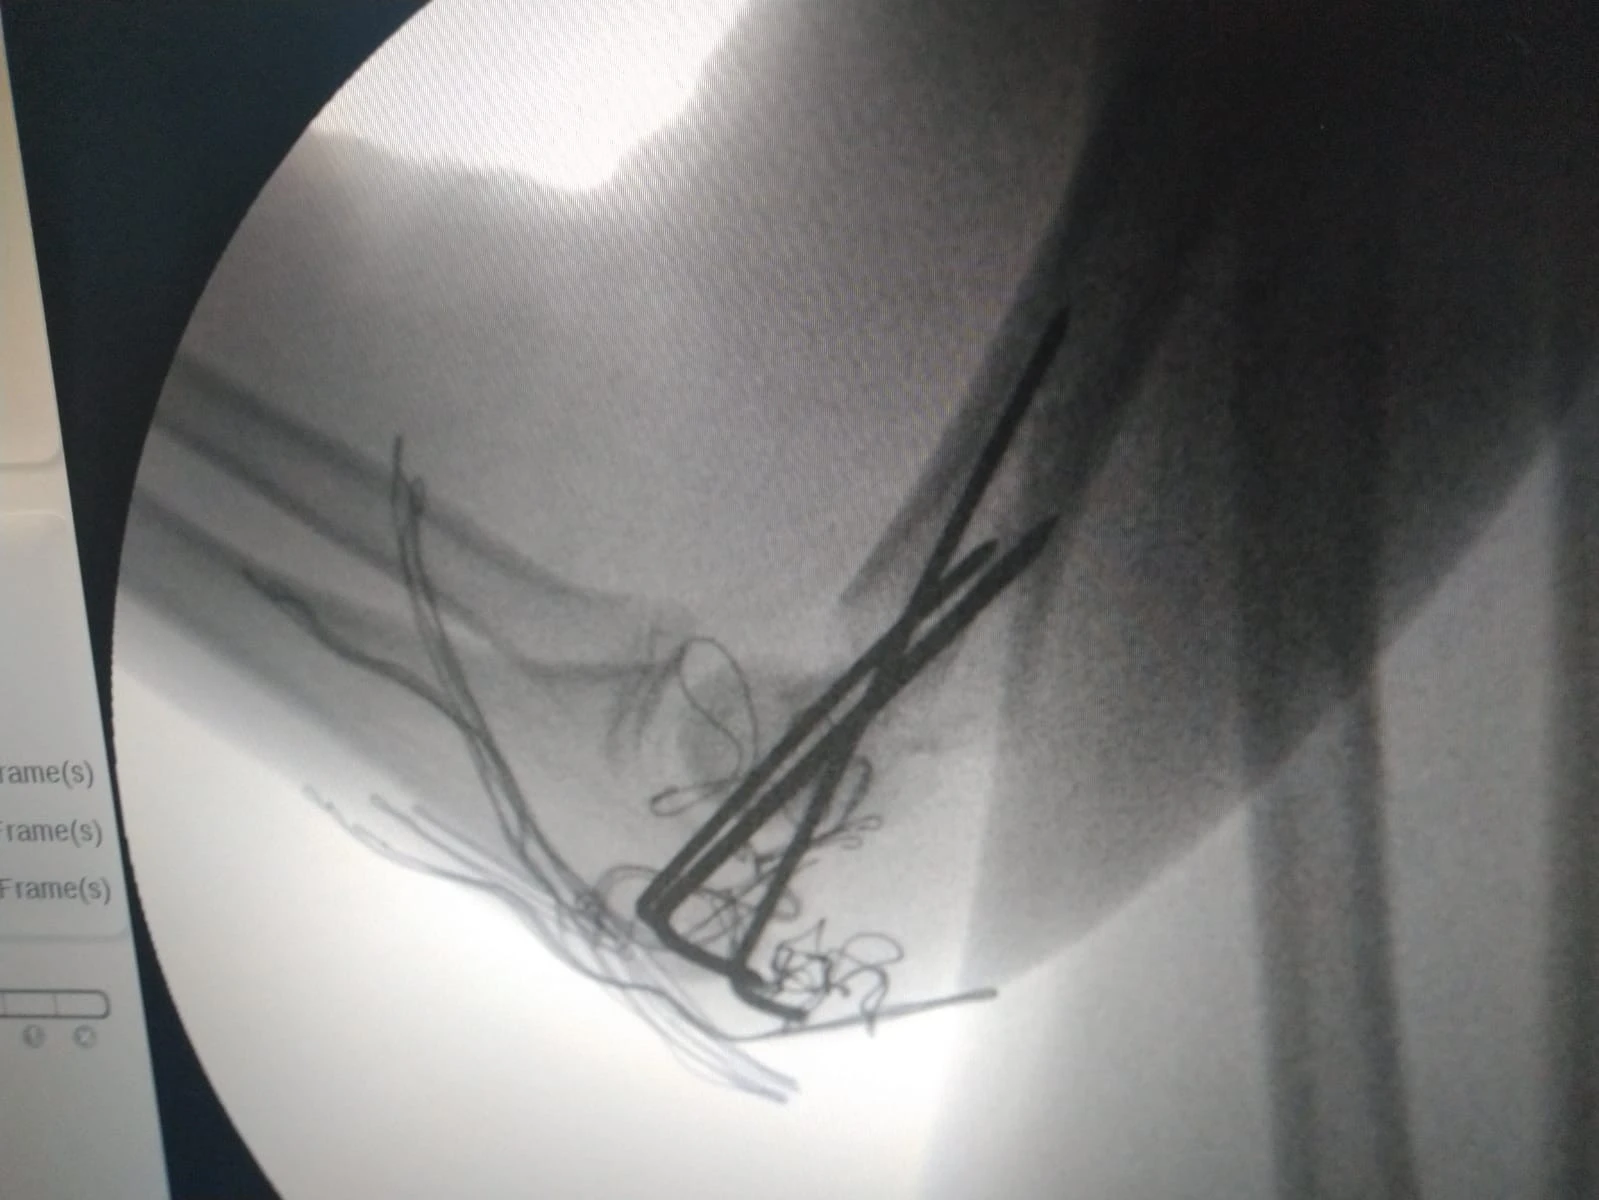

İlk kez bir Türk doktor tarafından gerçekleştirilen ve çocuk dirsek kırıklarının kapalı tedavisi için geliştirilen yeni bir ameliyat tekniği, Journal Of Klinical Medicine dergisinde yayımlandı.

Ortopedi ve Travmatoloji Uzmanı Dr. Mustafa Kınaş ve Uz. Dr. Ozan Turhal tarafından 46 hasta üzerinde başarılı bir şekilde uygulandıktan sonra makale haline getirilen teknik, tek hekim tarafından kolayca tatbik edilen ve başarılı sonuçlar alınan bir teknik olarak tıp literatüründeki yerini aldı.

Böyle bir ameliyatın tek hekimle yapılmasının çok zor olduğunun altını çizen Uz. Dr. Mustafa Kınaş, geliştirmiş olduğu bu teknikle kolayca başarılı sonuçların alınabildiğini söyledi. Yaptığı çalışma hakkında bilgi veren başarılı Mustafa Kınaş, “Çocuk dirsek kırıkları çok sık karşılaşılan kırık çeşitleridir. Genellikle ameliyat edilmesi gereken kırıklar olarak karşımıza çıkar. Bu kırıklar açık ve kapalı olarak ameliyat edilir. Tedavisi zor ve genellikle 2 ortopedi uzmanının beraber yardımlaşacak yaptığı bir ameliyat çeşididir. Biz zorunlu hizmette bu hastaları tek başımıza ameliyat ederken, arkadaşımız Uz. Dr. Ozan Turhal benim ameliyatımı gördü. Tek başıma yapmış olmama şaşırdı ve bu tekniğin dünya kütüphanesine eklenmesi gerektiği fikrini ortaya attı. Süreç bundan sonra başladı. Yaklaşık 46 hasta üzerinde çalışma yaptık. Hastaları tedavi ettik ve takibini yaptık. Tedavi ve sonuçlarını yazarak makalemizi dergiye gönderdik. Bu tekniğin literatürde ilk olması sebebiyle çok çabuk bir şekilde kabul edildi ve yayınlandı” dedi.

Kınaş, şu an çalıştığı hastanede 2 hastayı da bu teknikle ameliyat ederek başarılı neticeler aldı.